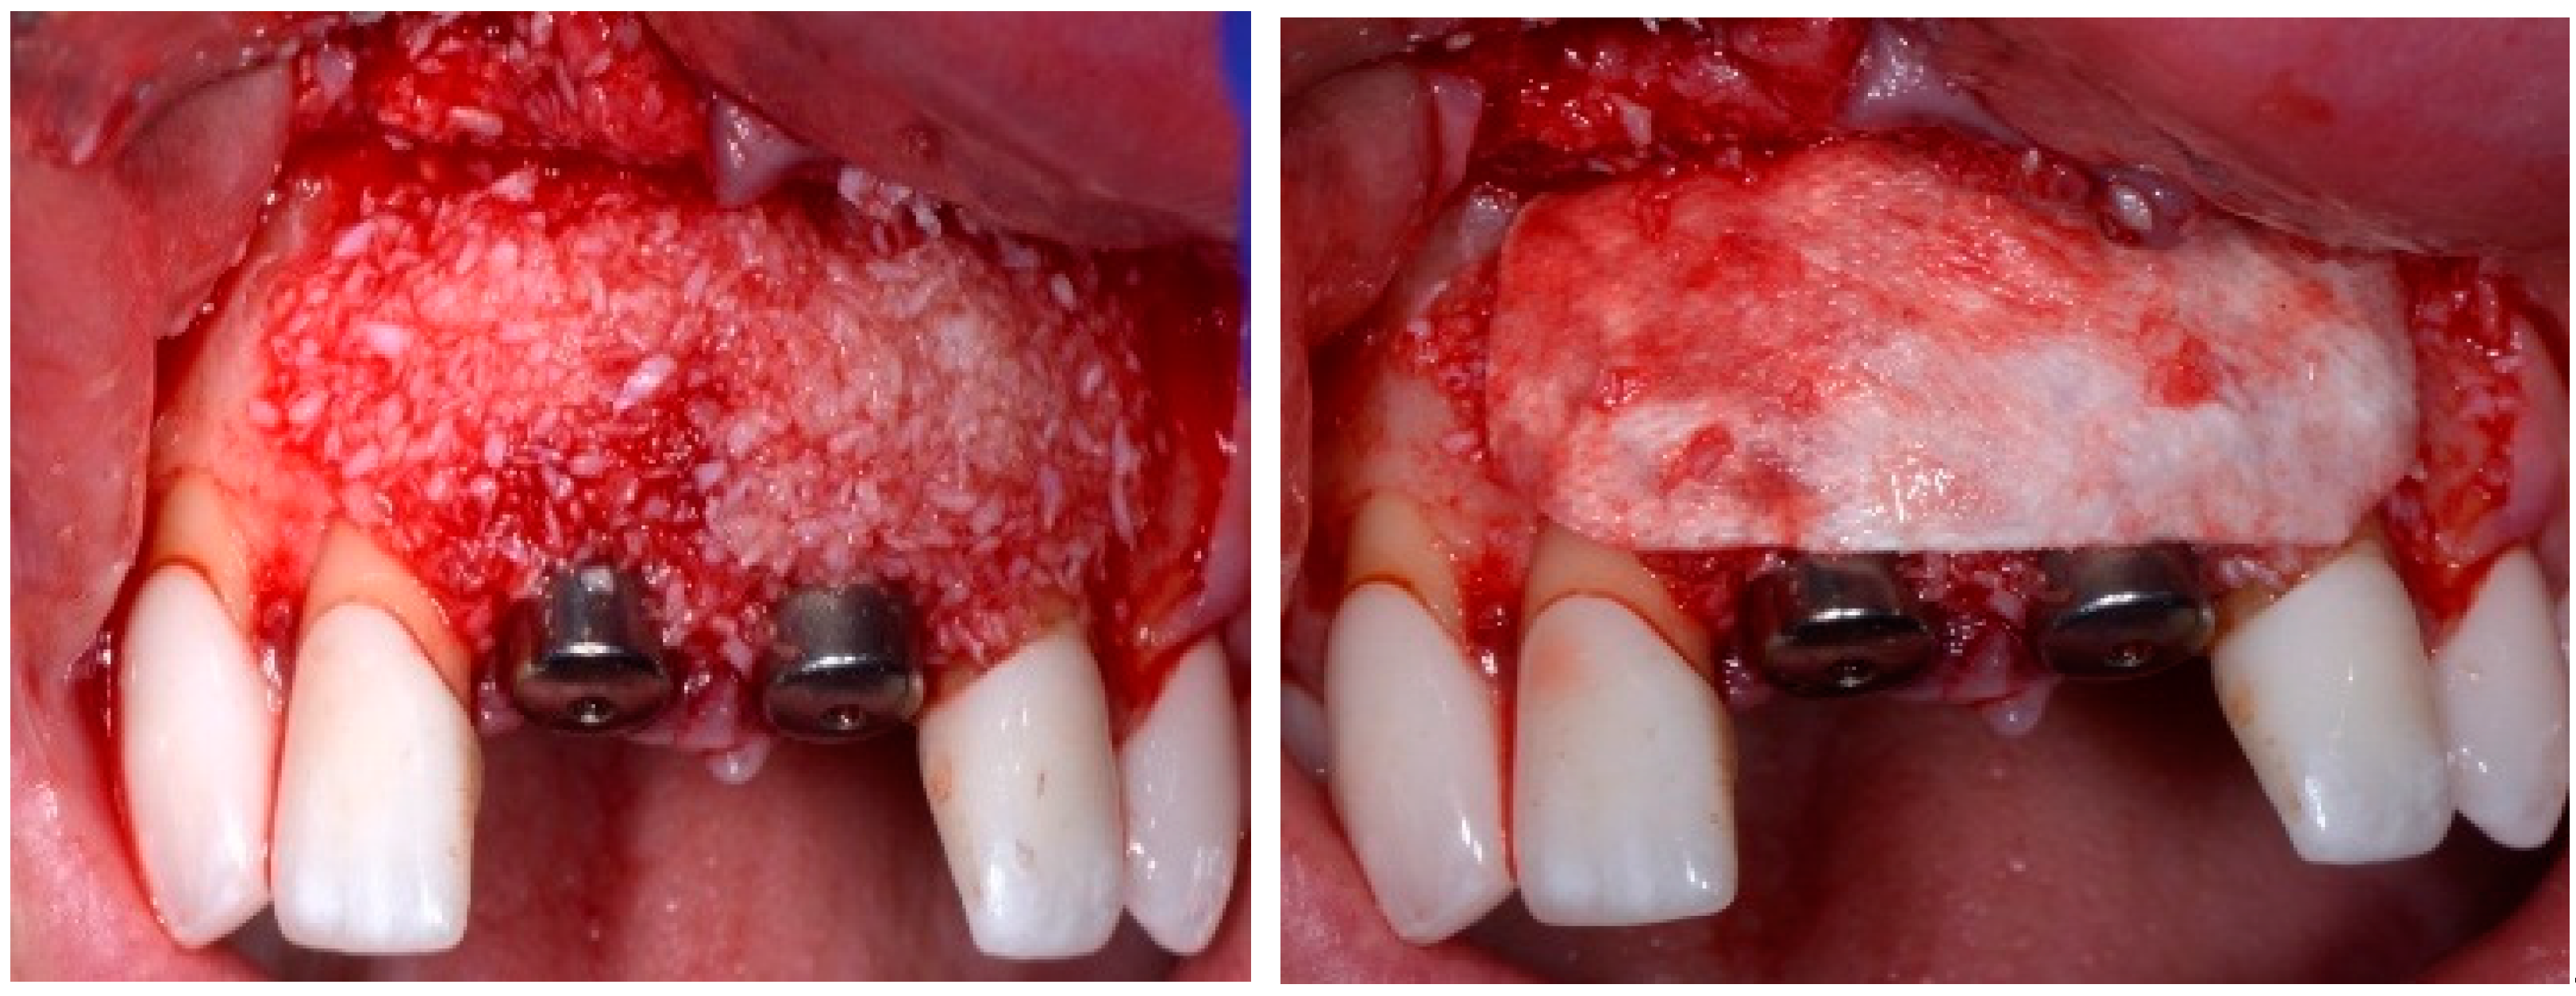

One hour before the surgical procedure, the patient received a prophylactic dose of 1 g of amoxicillin. Following local anesthesia, surgical access was obtained by raising a full-thickness aesthetic flap extending to the distal line angles of the lateral incisors. The full-thickness flap was extended 3–5 mm beyond the apical margin of the defect. The two central incisor roots were extracted, and the sockets were curetted with surgical curettes to remove all the granulation tissue (Figure 2). The sockets were assessed for the presence of a dehiscence and or fenestration. Two implants (Adin Dental Implants, Englewood, NJ, 07632, USA) were placed according to the manufacturer’s instructions (Figure 3).

Figure 2.

Clinical view immediately after extraction.

Before the graft and membrane is placed over the defect, a periosteal dissection must be performed to release flap tension to facilitate its coronal advancement and closure. The horizontal incision is made 1 mm deep into the periosteum, apical to the mucogingival junction, in a single plane along the length of the flap, connecting the two vertical releasing incisions. After the placement of this shallow incision, a micro-elevator is used to stretch within the incision line. This stretching not only releases the tension within the flap but also allows a more coronal advancement of the flap margin for eventual primary closure, minimizing postoperative incision line opening. This important step in flap management is performed before the placement of the graft material because the periosteal-releasing incision is associated with increased bleeding, which will complicate the graft, the membrane placement, and stabilization. A composite graft material consisting of allograft and xenograft in a 50/50 mix was placed in the gap between the implant and the socket wall over-contouring the facial wall defect (Figure 4). Two healing abutments were placed on the implants, followed by a bioabsorbable collagen membrane (Zmatrix, Osteogenics, Lubbock, TX 79424, USA) placed over the surgical area, which was closed with 5.0 polypropylene sutures (Figure 5). An Essex appliance, fabricated inhouse using a standard suck-down process, was inserted postsurgically. The implants were allowed to heal in a non-submerged environment for a period of 6 months.

Figure 4.

Clinical view post graphing.